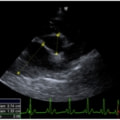

D:超音波写真 狭窄部の異常血流速度の測定

1年ほど前より左側胸壁からLevine 3/6の心雑音が聴取されていた。雑音の精査のため、心エコー検査を行ったところ、左室流出路の狭窄を伴う肥大型心筋症(閉塞型肥大型心筋症)と判明した。心室の拡張性を上げるため、βブロッカーであるカルベジロールを用いた治療を行っている。肥大型心筋症は犬の心疾患のように、心拡大を認めないことも多く、レントゲン写真のみで心疾患の有無を判断する事が出来ない。また、閉塞を伴わない肥大型心筋症と異なり、閉塞型の本疾患の治療に対し、Caチャネルブロッカーは推奨されない。